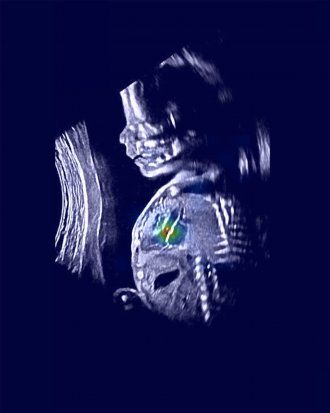

fetal ultrasound with area of the heart highlighted in different colors

An ultrasound image shows a normal fetus with relevant heart structures precisely highlighted. Image by Rima Arnaout